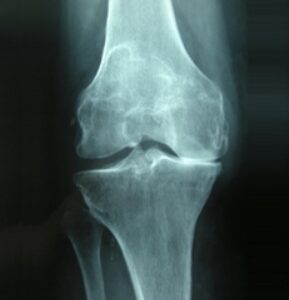

L’artrosi L’artrosi è una malattia degenerativa cronica che colpisce le articolazioni. È caratterizzata da un assottigliamento delle cartilagini fino ad arrivare al contatto dei capi articolari. In base alla gravità, si identificata l’artrosi di primo grado, secondo grado, terzo grado (quest’ultimo è il più grave). Per la diagnosi medica si possono eseguire esami strumentali come...